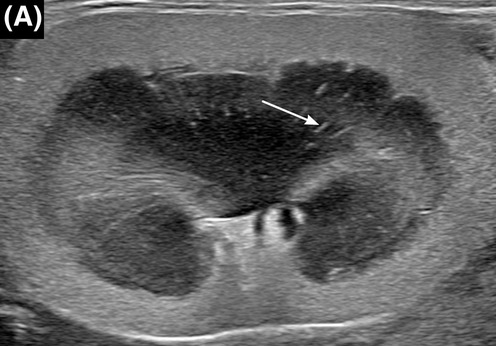

고양이 신장 초음파상 흰색 줄이 보인다면?

화살표처럼 수질부에 수직으로 고에코성 줄무늬가 간혹 보일 수 있는데 이것이 있을때 무엇을 의심해야 하는가, 혹은 의심해도 되는가에 대한 논문이 나왔다. 일반적인 medullary rim sign과는 다른 병변이다.

단백뇨와 요로계 감염과 관련이 있다는 결론이 나왔다.

즉, 건강검진상에서 해당 양상의 병변이 초음파 검사상 관찰된다면 뇨검사 및 지속적인 신장 평가를 위한 모니터링이 필요하다는 말.